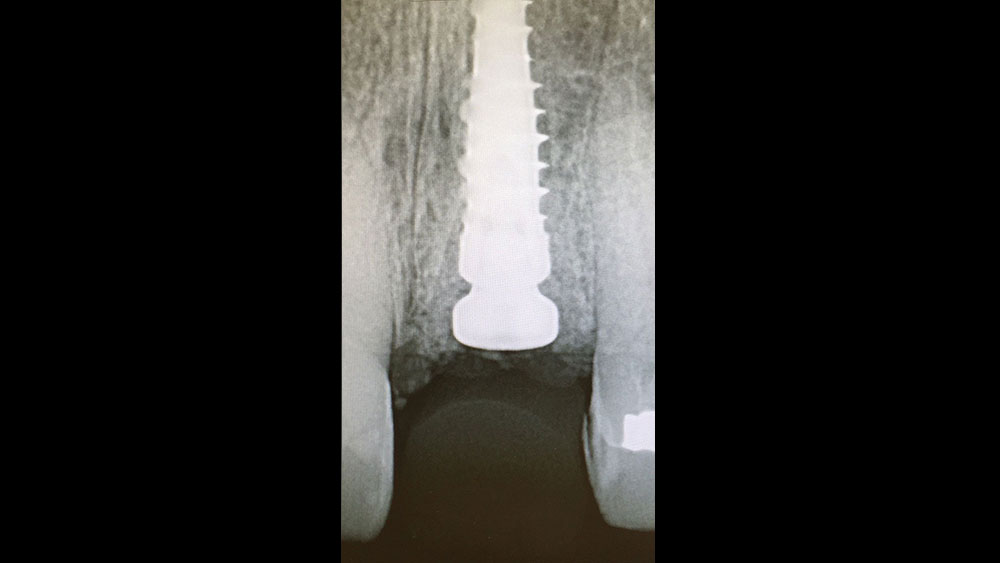

cm1401-rd-corner-efficacy-hahn-tapered-system-04a

cm1401-rd-corner-efficacy-hahn-tapered-system-04b

Figures 4a, 4b: Hahn Tapered Implants have multiple features that contribute to bone preservation and health, including coronal microthreads (4a) and a resorbable blast media surface (4b).

• Coronal microthreads, which help maximize bone-implant contact with an increased surface area, have been proven to increase crestal bone preservation.2,3,4

• The implant is treated with resorbable blast media (RBM), which involves a blasting process that texturizes the titanium surface of the implant and results in an ultra-clean, rough surface that has been proven ideal for bone integration and health.5

• In cases where bone loss occurs and the neck of the implant is exposed, the smooth metal surface of the implant’s machined cervical collar reduces attachment of biofilm, further assisting in bone preservation.15